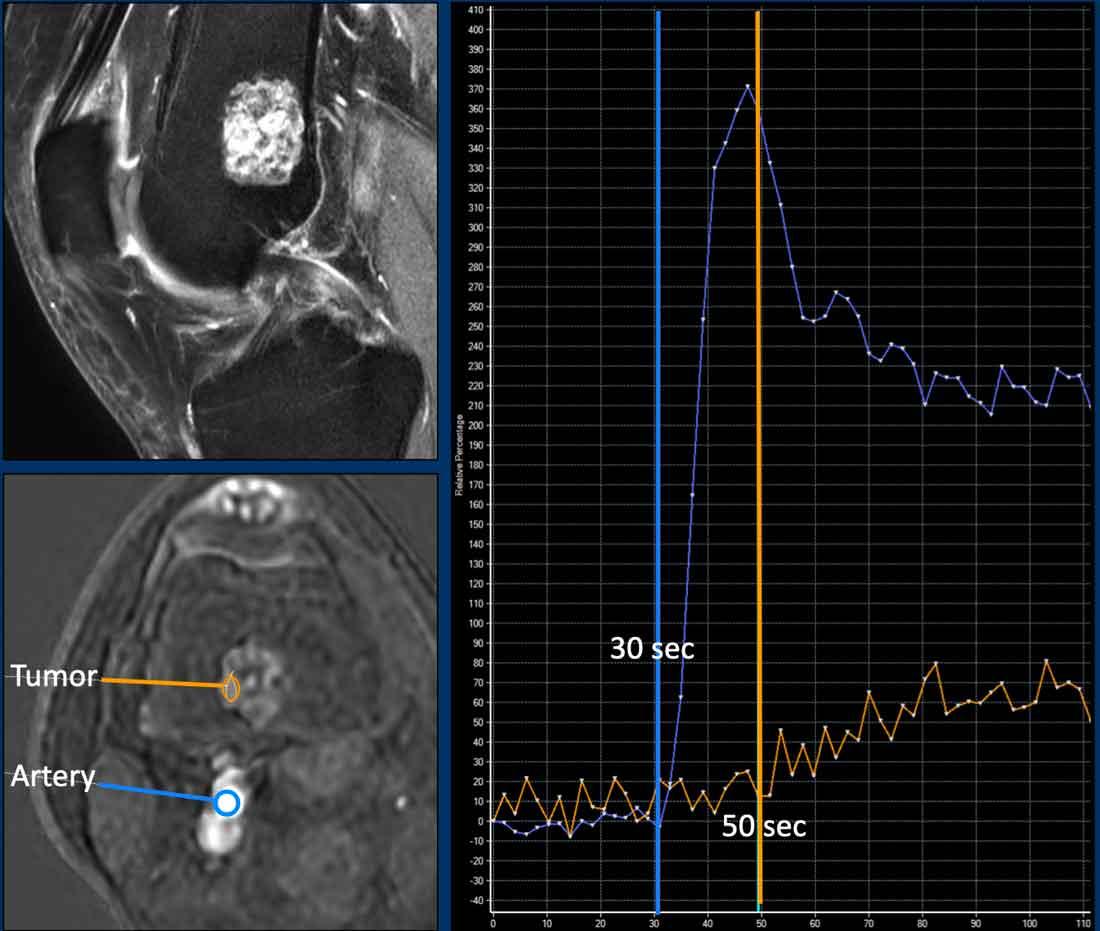

Tưới máu MR

Tưới máu hay MRI tương phản động là một kỹ thuật chẩn đoán hình ảnh chức năng trong đó sự ngấm thuốc sớm của khối u được theo dõi sau khi tiêm bolus gadolinium tĩnh mạch.

Trong các khối u sụn, tưới máu đã được sử dụng để phân biệt u sụn nội xương với u sụn ác tính.

Ngưỡng cắt 10 giây được sử dụng để phân biệt tăng ngấm thuốc nhanh và chậm. Tuy nhiên, có thể xảy ra sự chồng lấp trong các kiểu tăng ngấm thuốc sớm của các khối u sụn, ví dụ: u sụn lành tính (enchondroma) có thể tăng ngấm thuốc nhanh, nhưng cũng có các khối u sụn không điển hình (ACT) tăng ngấm thuốc chậm.

Hình ảnh

Có một khối u nhỏ hơn 2 cm ở hành xương đầu xa xương đùi.

Tổn thương tăng tín hiệu trên T2, đồng tín hiệu trên T1 và có ngấm thuốc dạng vách-nốt. Không có liên quan đến vỏ xương. Trên hình ảnh tưới máu (đường cong thời gian – cường độ tín hiệu), khối u cho thấy sự ngấm thuốc chậm, bắt đầu khoảng 20 giây sau khi động mạch ngấm thuốc.

Đây là u sụn trong xương và không cần theo dõi.

MR perfusion

ACT along the posterior cortex in the distal femur showing septonodular enhancement after contrast. Two ROIs were placed, one in the tumor (orange) and one in the popliteal artery (blue).

MRI tưới máu là một kỹ thuật chẩn đoán hình ảnh chức năng trong đó quá trình ngấm thuốc sớm của khối u được theo dõi sau khi tiêm bolus gadolinium tĩnh mạch.

Kỹ thuật này cung cấp thông tin về sự mạch hóa và tưới máu, tính thấm mao mạch và thể tích khoang kẽ.

Kỹ thuật này được sử dụng cho các khối u mô mềm và xương (chủ yếu tại các trung tâm ung thư chuyên biệt) trên toàn thế giới, và có thể hỗ trợ ví dụ như trong việc lựa chọn vùng không hoại tử để sinh thiết, hoặc để phân biệt tái phát tại chỗ với mô hạt. Tưới máu có thể giúp đặc trưng hóa các tổn thương và phân biệt tổn thương lành tính với ác tính.

MRI tưới máu thực chất có nghĩa là bạn đánh giá sự xuất hiện và thải trừ của thuốc tương phản gadolinium trong khối u theo thời gian.

Để thực hiện điều này, cần thu nhận các hình ảnh rất nhanh với độ phân giải thời gian cao (mỗi 2 hoặc 3 giây), trong khi thuốc tương phản đi vào và rời khỏi khối u trong tổng thời gian từ 3 đến 5 phút.

Sau khi thu nhận các hình ảnh động, giao thức thường được hoàn thành bằng các chuỗi xung tĩnh sau tiêm thuốc tương phản trên 2 mặt phẳng khác nhau.

Sử dụng phần mềm xử lý hậu kỳ, một vùng quan tâm (ROI) được vẽ trong một động mạch gần khối u. Tiếp theo, một hoặc nhiều ROI được vẽ trong khối u và trong một cơ lành để tham chiếu.

Các ROI khác nhau này sau đó được vẽ trên đường cong cường độ theo thời gian (TIC).

Trong các khối u sụn, tưới máu được sử dụng để phân biệt u sụn lành tính (enchondroma) với ung thư sụn (chondrosarcoma).

Ngưỡng cắt 10 giây được dùng để phân biệt ngấm thuốc nhanh và ngấm thuốc chậm. Tuy nhiên, có thể xảy ra sự chồng lấp trong các kiểu ngấm thuốc sớm giữa ung thư sụn (CS) và u sụn lành tính, ví dụ: một số u sụn lành tính có thể ngấm thuốc nhanh, nhưng cũng có những khối u sụn ác tính độ thấp (ACT) ngấm thuốc chậm.

Ví dụ về một ACT tăng cường chậm (đường màu cam), hơn 10 giây sau động mạch (đường màu xanh lam).